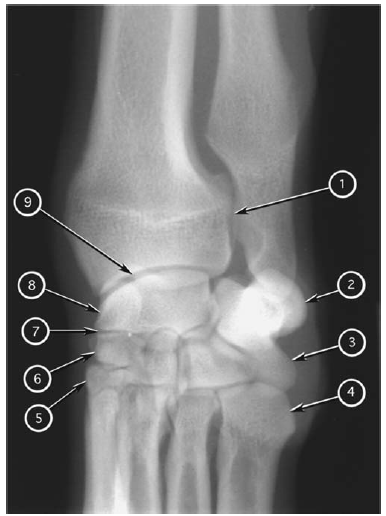

Craniocaudal radiograph of canine antebrachium

What number?

- Medial epicondyle of humerus

- Lateral epicondyle of humerus

- Head of radius

- Body of radius

- Distal metaphysis of radius

- Distal epiphysis of radius

- Body of ulna

- Distal metaphysis of ulna

- Distal epiphysis of ulna (styloid process)

- Medial coronoid process of ulna

- Ulnar carpal bone

- Intermedioradial carpal bone

- Elbow (cubital) joint

- Sesamoid bone of abductor pollicis longus

A

1. Medial epicondyle of humerus

2. Medial coronoid process of ulna

3. Body of radius

4. Distal metaphysis of radius

5. Distal epiphysis of radius

6. Intermedioradial carpal bone

7. Sesamoid bone of abductor pollicis longus

8. Ulnar carpal bone

9. Distal epiphysis of ulna (styloid process)

10. Distal metaphysis of ulna

11. Body of ulna

12. Head of radius

13. Elbow (cubital) joint

14. Lateral epicondyle of humerus